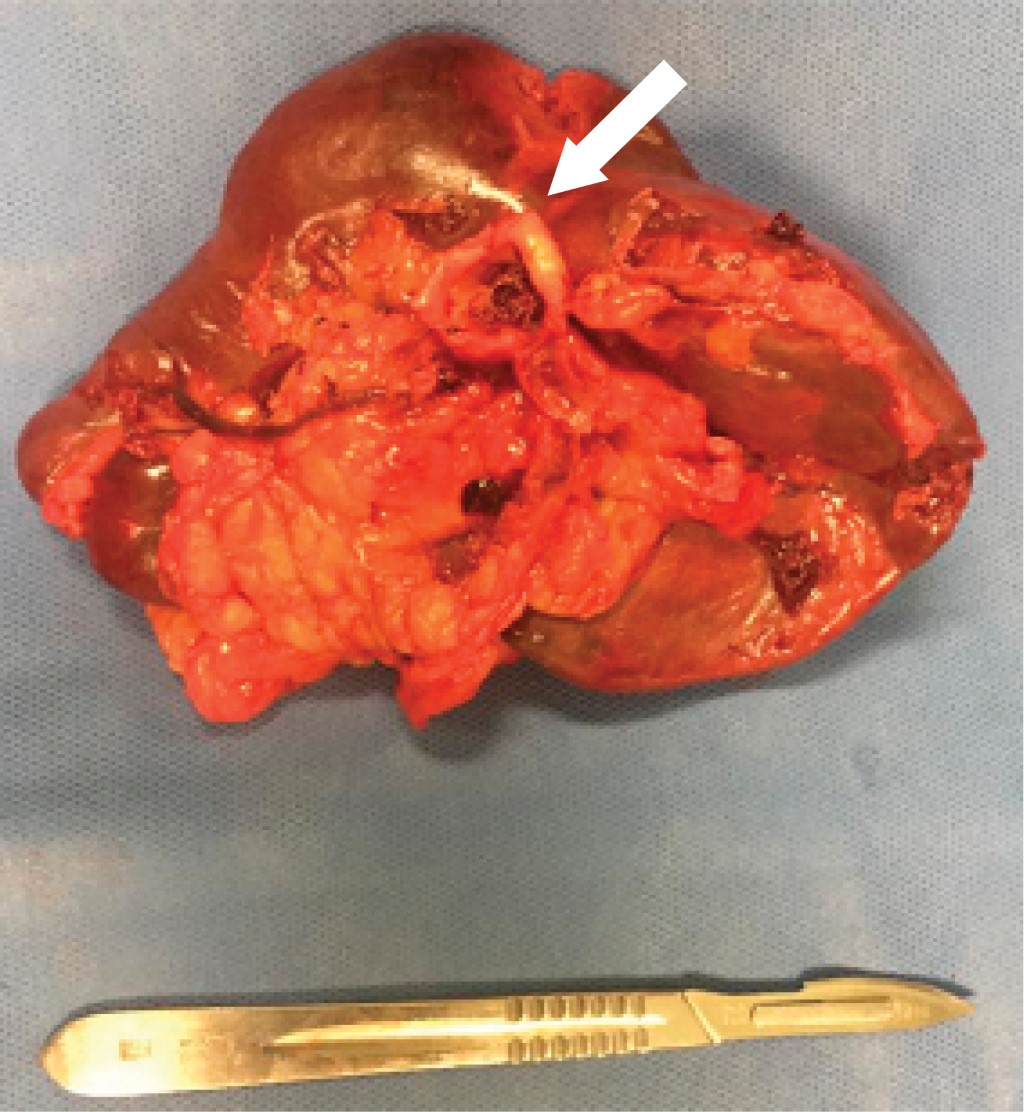

This was a 41-years old female patient with a history of hypothyroidism diagnosed at 21 years old, currently without medical treatment for 40 years old due to apparent control, diagnosis of uterine myomatosis at 40 years old, without treatment; history of two cesarean sections, being the last one at 23 years old, without complications. She suffered a car accident with rollover at age 40, without apparent organic damage. She began her current condition after a car accident one year earlier with intermittent, stabbing, non-radiating pain in the left hypochondrium, with no aggravating or extenuating factors; on physical examination, she presented pain in the left hypochondrium on deep palpation, with no other pathological findings. Ultrasound was performed with results compatible with an aneurysm of the splenic artery and cholelithiasis; the diagnostic approach was complemented with angio-tomography of the abdominal aorta finding a splenic artery of standard caliber, with focal saccular dilatation in distal segment compatible with an aneurysm of 17.7 × 15.9 mm and neck of 5.5 mm, with mural thrombus of 2 mm, with no signs of rupture; vesicular lithiasis and uterine myomatosis were also seen. With no apparent complications, selective embolization with coil placement was performed in conjunction with angiology (Figure 1). In the immediate follow-up, the patient presented abdominal pain and leukocytosis; a new angio-tomography was performed with data suggestive of splenic artery occlusion and splenic infarction (Figure 2). Due to the findings mentioned above, it was decided to perform splenectomy and conventional cholecystectomy using a surgical approach with a midline supraumbilical incision, with the following findings: Thin-walled gallbladder, multiple calculi inside of 5-10 mm approximately, cystic artery of 2 mm, cystic duct of 3 mm, spleen of 13 × 10 cm approximately, with multiple ischemic areas, an aneurysm of the splenic artery at the level of the splenic hilum, posterior to its bifurcation (Figure 3). The postoperative course was without complications, so she was discharged three days after surgery and received the corresponding vaccination for patients with splenectomy. The histopathological report included findings of splenic artery aneurysm with atherosclerosis, splenic parenchyma with congestive vessels, and chronic calculous cholecystitis.

Being a patient who presented symptoms associated with the pathology, it was decided to initiate treatment in the least invasive way, performing selective embolization and placement of coils by the Angiology Service. However, she presented a torpid post-surgical evolution, requiring a new angio-tomography, in which an extensive area compatible with infarction was visualized, offering a poor response to minimally invasive treatment. So, it was decided to carry out a more invasive treatment and scheduled splenectomy and conventional cholecystectomy. The literature refers to the next step in the treatment of this patient, a laparoscopic intervention secondary to the failure of minimally invasive treatment. However, laparoscopy was unavailable in our unit then, so the treatment was performed by open or conventional surgery.

Figure 3